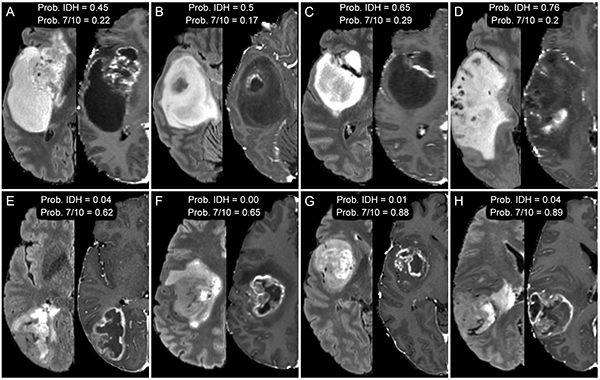

A new study from scientists at UCSF Radiology and Biomedical Imaging uses artificial intelligence (AI) to predict the presence of specific genetic alterations in individual patient's tumors using only non-invasive brain MRI. Using this AI-driven "virtual biopsy" approach, they were able to accurately identify several clinically relevant genetic alterations including some that are under investigation as potential treatment targets.

The work represents an important step towards a fully automated method for non-invasive, imaging-based identification glioblastomas with IDH mutations and certain other molecular biomarkers relevant for guiding therapy and determining prognosis. The study itself was a small, retrospective study; however, the rapid and automated nature of the proposed method from UCSF Radiology scientists would allow straightforward application to larger datasets and prospective studies.